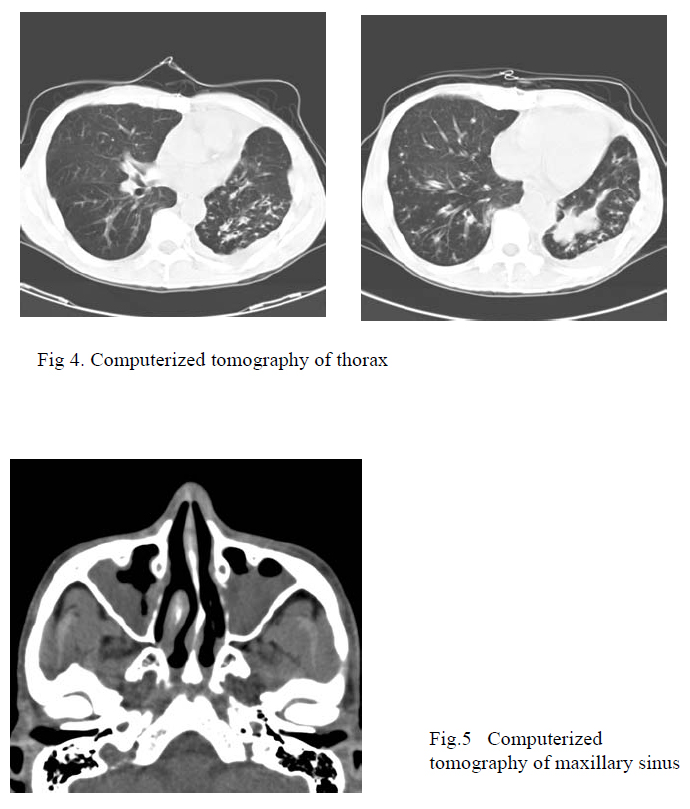

Sputum for AFB smear and culture and Pneumocystic jiroveci were negative. Sputum for fungal culture grew Candida species which was accounted by the presence of oral candidiasis. Repeated HIV Ab testing was negative. Blood for atypical pneumonia titer and CMV pp65 were also negative. Repeated CT thorax showed collapse consolidation of left upper lobe and dilated bronchi in right lower lobe and left lower lobe suggestive of bronchiectasis (Fig.4). There were no mediastinal lymph nodes or pleural effusion. CT sinus revealed mucosal thickening and high density fluid was filling both maxillary sinuses bilaterally suggestive of sinusitis (Fig.5). He was seen by ENT and given Metronidazole and Ciprofloxacin for 10 days and no need for drainage. USG abdomen was unremarkable.